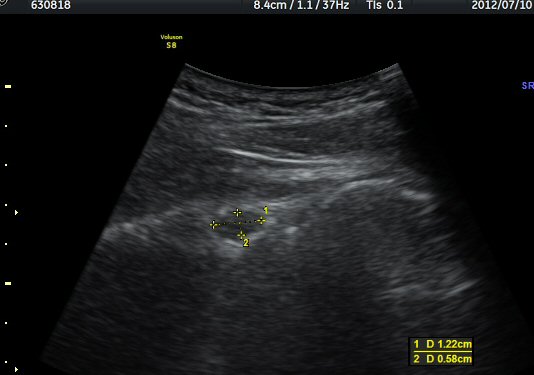

ÃÊÀ½ÆÄ °Ë»ç

¾î±ú °üÀý µÚÂÊ ÈĹæ°üÀý¼ø Ⱦ´Ü¸é°Ë»ç¿¡¼­ °üÀý¼ø ³»Ãø, °¡½Ãµ¹±â°üÀý¼ø°í¶û(spinoglenoid

notch)¿¡¼­ Àú¿¡ÄÚ ³¶Á¾ÀÌ °üÂûµÈ´Ù(±×¸² 1). ŽÃËÀÚ¸¦ À§-¾Æ·¡ ¹æÇâÀ¸·Î º¯°æÇÏ¿© °üÂûÇÒ ¶§µµ

¿ª½Ã °ß°©°ñ °¡½Ãµ¹±â(spine) ¾Æ·¡¿¡¼­ Àú¿¡ÄÚ ³¶Á¾ÀÌ °üÂûµÈ´Ù(±×¸² 2). º¼·ÏŽÃËÀÚ·Î ¹Ù²Ù¾î °ü

ÂûÇÏ´Ï  °¡½Ãµ¹±â°üÀý¼ø°í¶û¿¡¼­ Àú¿¡ÄÚ ³¶Á¾ÀÌ ´õ¿í ¶Ñ·ÈÈ÷ °üÂûµÈ´Ù(±×¸² 3, 4).